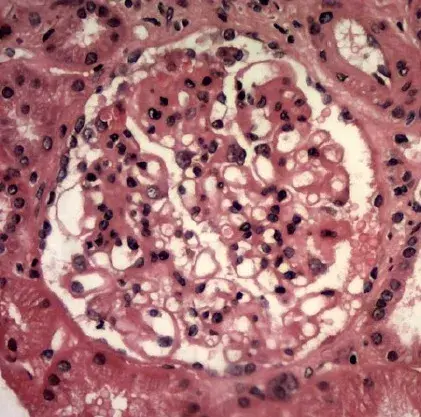

Caso clínico publicado no **[NEJM](https://www.nejm.org/doi/full/10.1056/NEJMicm2213584?query=featured_nephrology)**: Um homem de 35 anos com nefropatia por IgA procurou pronto-socorro com quadro de confusão mental, visão embaçada e convulsão há 01 dia. Duas semanas antes da apresentação ele começou a tomar ciclosporina para tratamento de nefropatia por IgA. Sua PA era de 160/80 mm Hg.